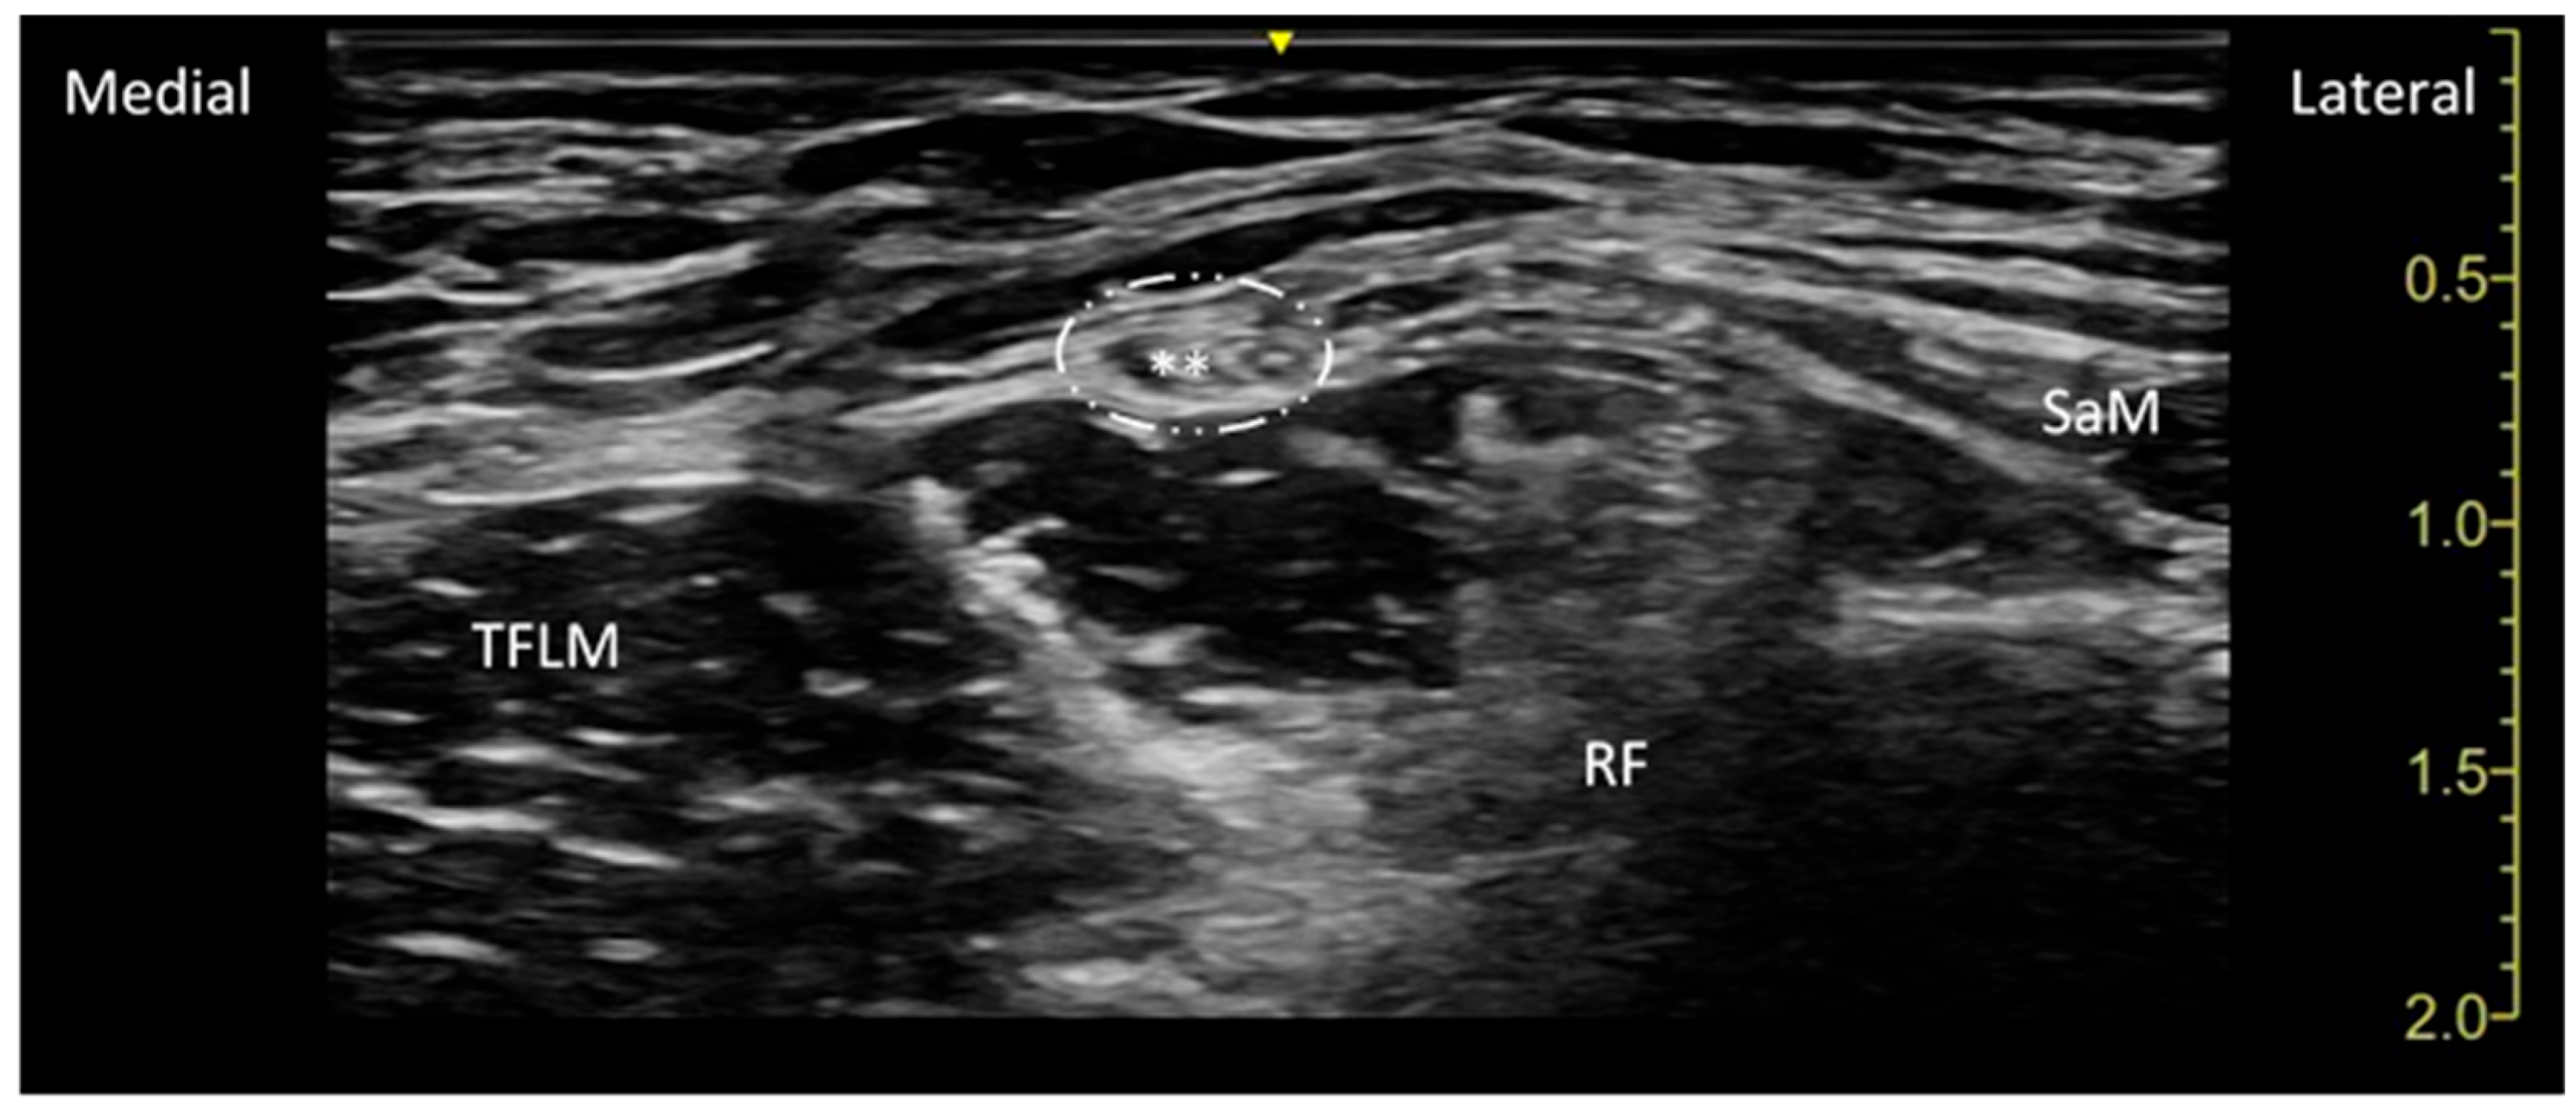

| SaM | Sartorius muscle |

| TFLM | Tensor fascia latae muscle |

| RF | Rectus Femoris Muscle. |